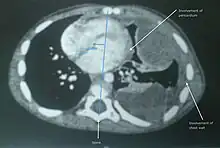

| Undifferentiated soft tissue sarcoma in left lung of young child | |